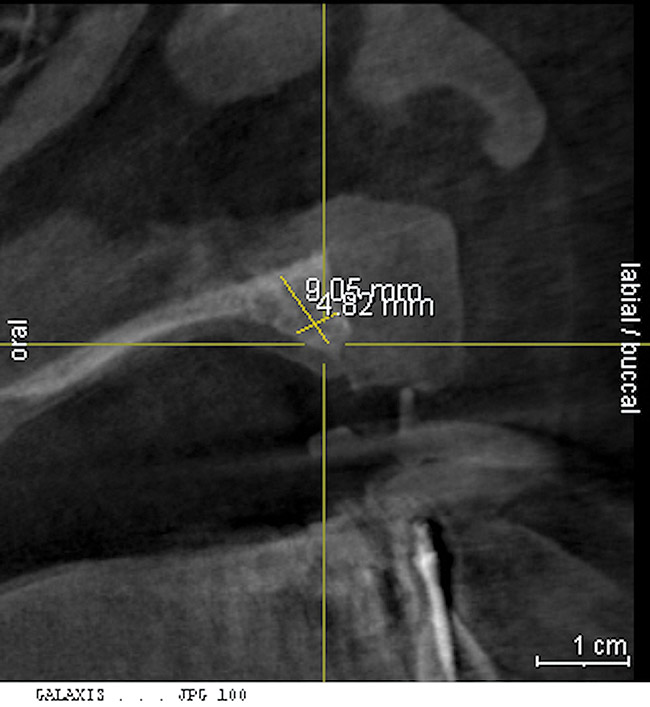

Figure 2 Cone-beam CT scan revealed severe horizontal bone deficiency in the proposed implant position.

Figure 2

A 26-year-old woman presented with a history of trauma combined with an impacted maxillary right canine (No. 6), which was extracted in early childhood. Following two courses of orthodontic therapy—one in her early teens and the second in early adulthood—the area had reportedly been grafted approximately 9 months prior to her initial presentation to the author’s private periodontal practice. Clinically, the edentulous site appeared healthy, with significant keratinized mucosa in the canine position (Figure 1). A cone-beam CT scan revealed severe horizontal bone deficiency in the proposed implant position (Figure 2). Adequate bone height for implant placement was evident; however, the thinnest portion of the ridge measured approximately 0.45 mm in width. It was proposed that an augmentation be performed to facilitate implant placement, which the patient accepted.

Approximately 4 months after grafting, the patient returned for clinical and 3-D radiographic evaluation. The thinnest area of ridge width preoperatively was remeasured in approximately the same location, demonstrating a gain of about 4 mm (Figure 7). The treatment plan was to place a 3.5-mm x 13-mm implant with a computer-generated guide (SiCat, Sirona Dental, www.sironausa.com), eliminating an additional open surgical procedure. Planning included initial osteotomy preparation with single-use drills combined with a localized ridge expansion using narrow, tapered osteotomes. This was performed approximately 5 months after the augmentation procedure, achieving primary stability of the implant, facilitating a transmucosal healing approach (Figure 8 and Figure 9). Following each step of osteotomy preparation, a probe was inserted along the walls of the site to confirm the integrity of the buccal and palatal walls prior to implant insertion.